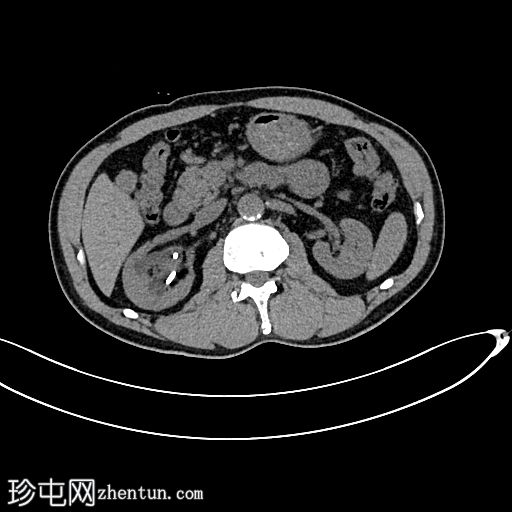

轴位

平扫

可见中度右肾积水和输尿管积水。右肾双极长10.6厘米。可见输尿管支架,近端位于肾上极肾盏,远端位于膀胱内。肾下极可见肾结石。肾下极可见肾皮质囊肿,囊壁薄,内含钙化。肾上极可见肾实质钙化。在支架旁远端输尿管(S1至S2椎体水平)可见少量输尿管结石。

左肾双极长9.2厘米。肾上极和肾下极可见微小结石。未见输尿管结石。无肾积水或输尿管积水。肾上极可见肾皮质囊肿。

膀胱轮廓正常。未见膀胱结石。